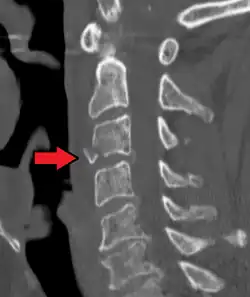

Radiographic detection

On CT scan or X-ray, a cervical fracture may be directly visualized. In addition, indirect signs of injury by the vertebral column are incongruities of the vertebral lines,[7] and/or increased thickness of the prevertebral space:[8]

![CT scan of normal congruous vertebral lines[7]](./Vertebral_lines.png)